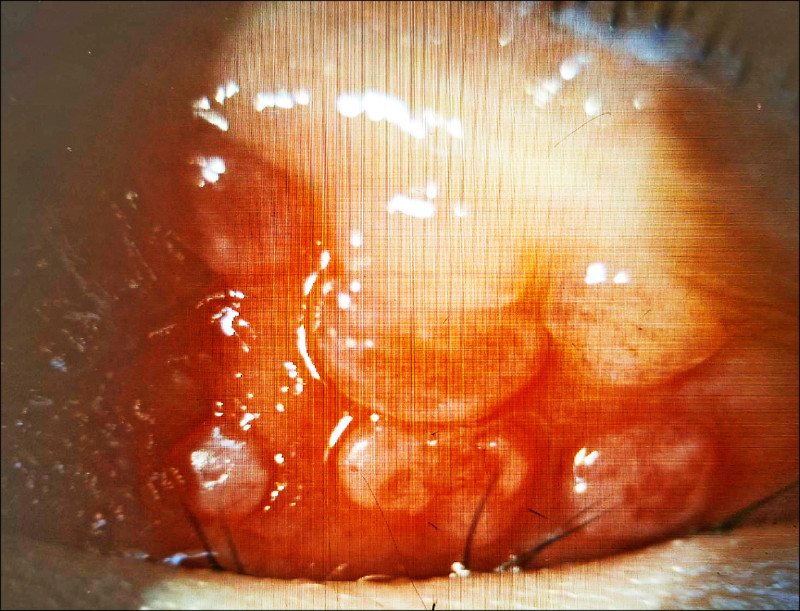

1名國小二年級男童近半年來常覺得左眼癢而不斷眨眼、揉眼,近日左眼嚴重腫脹,檢查發現上眼長了許多巨大的疙瘩物,並覆蓋白色黏液,診斷為「巨大乳突結膜炎合併角膜潰瘍」研判是過敏性結膜炎釀的禍。

巨大乳突結膜炎合併角膜潰瘍

達特楊眼科聯盟執行長洪啟庭指出,小二男童就醫時不僅左眼眼瞼嚴重腫脹、結膜發紅,最佳視力僅0.5並有300度散光,應是過敏性結膜炎過合併過敏性鼻炎、濕疹、異位性皮膚炎或氣喘等,慢性發炎加上長期揉眼,使得結膜上皮細胞增厚和絨毛結構的過度增生,長滿巨大乳突,長時間壓迫並造成上半部角膜有淺層潰瘍,因此導致300度的高度散光和視力模糊。

根據研究,台灣每3個學童就有1位罹患短期或長期性過敏性結膜炎,洪啟庭表示,短期多是季節性過敏,長期性如本案男童,因慢性發炎導致結膜上皮細胞的過度增生,長成大於0.1公分的乳突,病人會有明顯的異物感、激癢、黏液分泌物變厚、視力模糊、嚴重時還會出現角膜潰瘍,成人大多是和隱形眼鏡配戴習慣不良有密切關係,學童多是過敏反應造成。